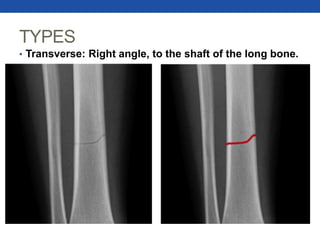

TYPES

• Transverse: Right angle, to the shaft of the long bone.